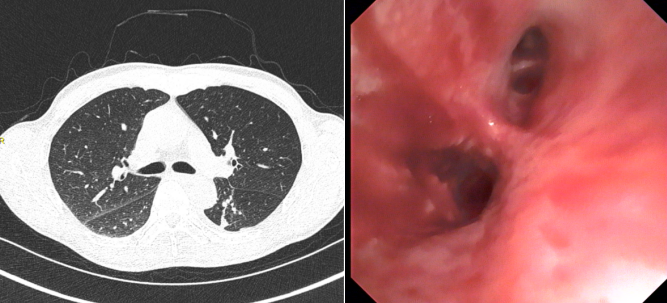

治疗前:CT影像及气管镜下所见